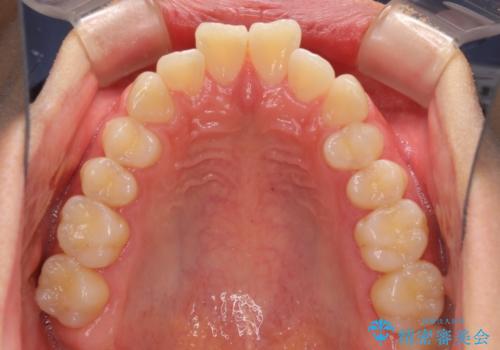

深い咬み合わせとデコボコ ワイヤー矯正で短期治療

- 前歯のデコボコを改善したいとのことで来院された患者様です。

結果として、1年かからずに奥歯の咬み合わせを改善することができました。